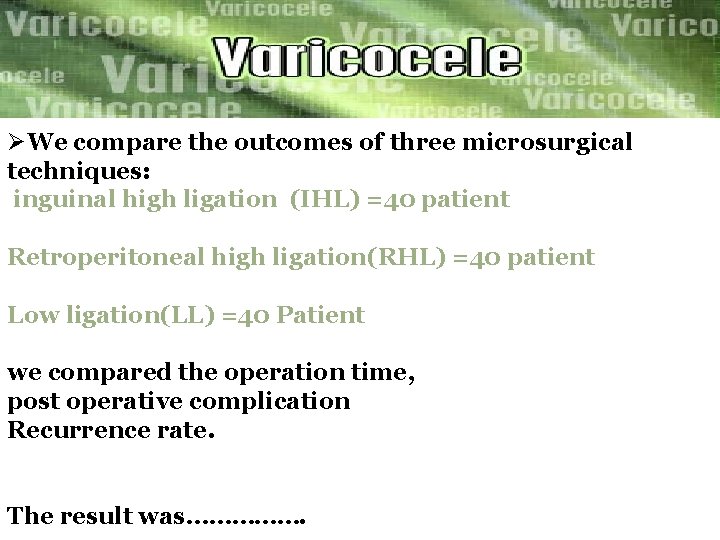

ØWe compare the outcomes of three microsurgical techniques: inguinal high ligation (IHL) =40 patient Retroperitoneal high ligation(RHL) =40 patient Low ligation(LL) =40 Patient we compared the operation time, post operative complication Recurrence rate. The result was…………….

Conclusion Ø As a microsurgical approach to the treatment Of varicocele , low ligation is better than inguinal High ligation and retroperitoneal high ligation in improving Recurrence rate and seminal parameters of the patients.